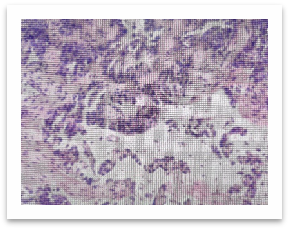

手术原始病理切片图

张艰教授团队当即决定,借出2020年手术的原始病理切片,重新读片。最终,病理复诊证实,当年的病灶为IA1期浸润性腺癌,含管状腺癌(70%)和恶性程度较高的微乳头状癌(30%)成分,还伴有气腔播散及少量脉管癌栓,这正是术后快速进展的关键。

张艰教授团队没有急着下结论,而是对王先生4年前第一次手术的肿瘤切片,重新做病理分析和免疫组化检测。结果发现,不是单纯的腺癌,里面混杂着鳞癌的成分。